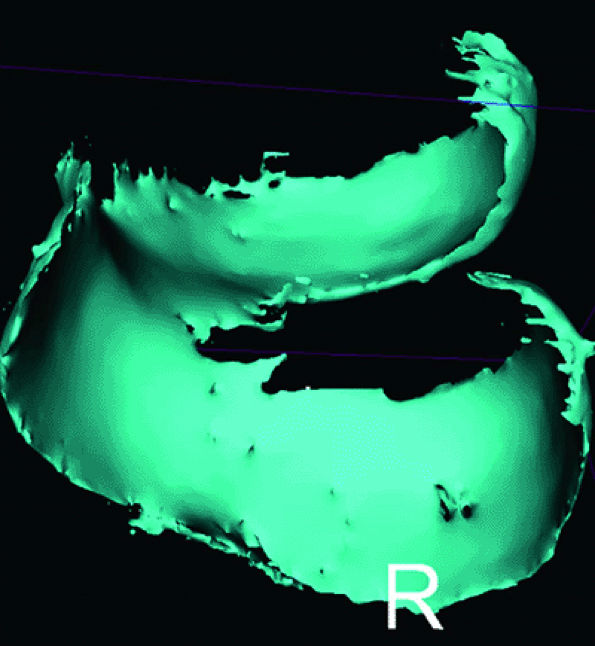

FIGURE 7.4 ● Three-dimensional cartilage model built from a semi-automated segmentation algorithm, with the cartilage subtracted from the subchondral bone. MR data were obtained from a 3D fat-suppressed, T1-weighted gradient-echo acquisition. These models may eventually prove helpful in surface replacement techniques.